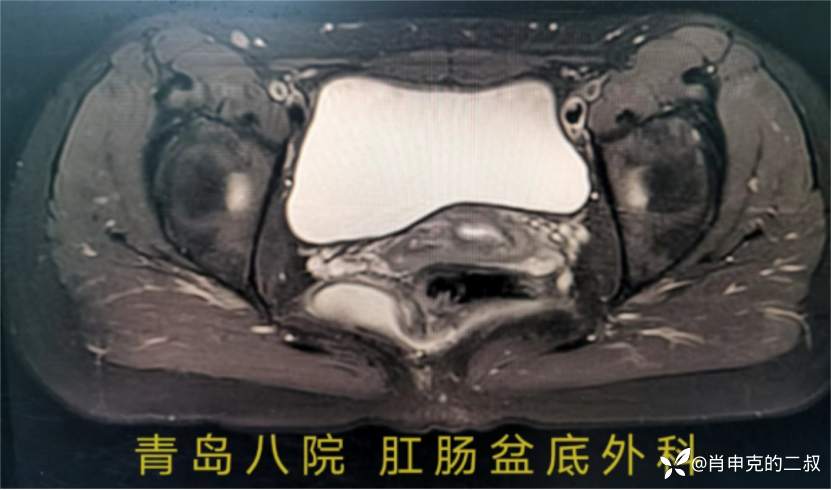

多次手术必然不会太容易,术前MR检查是此类患者的金标准,

通过MR我们发现患者并不是肛周脓肿